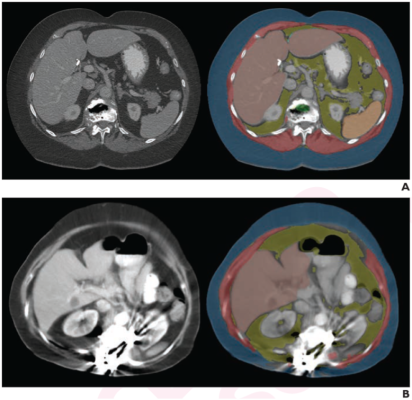

Examples of Specific Causes Identified for AI Tool Failure. Axial images at L1 level, without (left) and with (right) segmentation overlay. Red indicates skeletal muscle, green indicates trabecular bone, yellow indicates visceral fat, and blue indicates subcutaneous fat. Segmented regions also include liver (beige) and spleen (orange), which were not evaluated as part of present analysis. (A) 78-year-old woman who underwent abdominopelvic CT at outside institution. Bone tool returned L1 vertebral body bone attenuation of -146 HU, outside of reference range. Thus, tool was deemed technical failure for bone tool. Failure was attributed to volume averaging of vacuum phenomenon within slice. (B) 64-year-old woman who underwent abdominopelvic CT at outside institution. Bone tool returned vertebral body bone attenuation of -10,000 HU (default value for segmentation failure detected by tool), outside of reference range. Thus, tool was deemed technical failure for bone tool. Failure was attributed to presence of spinal fusion hardware.